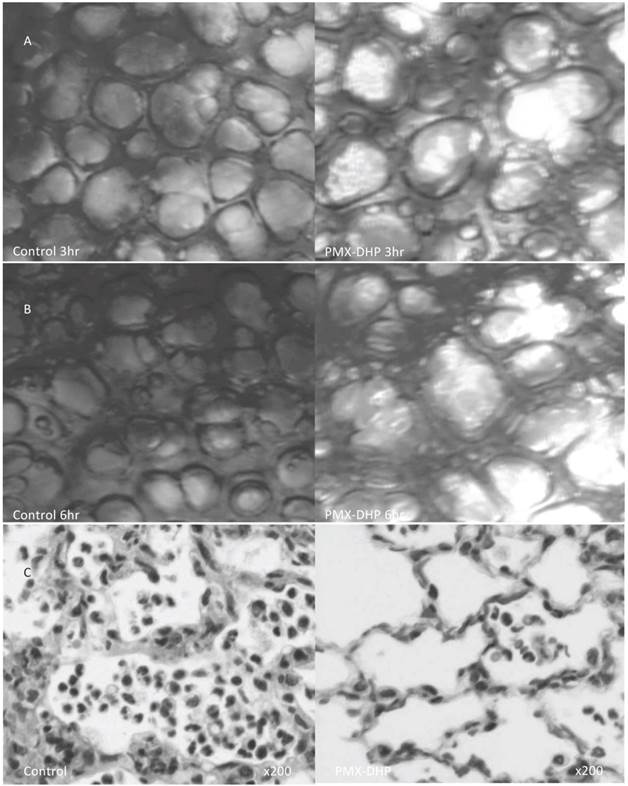

A low magnified view revealed cloudy alveoli with exudates in the control group (Fig. 2A), increasing over time. Meanwhile, the alveoli remained clear in the PMX-DHP group, even at 6 hours (Fig. 2B).

The pathological findings in H-E stained specimens were comparable to that of the intravital microscopic examination. Widespread neutrophil and platelet plugging in the capillary, infiltration to interstitial and intra-alveolar space and destruction of the lung parenchyma was observed in the control group, and these changes were kept less in the PMX-DHP group (Fig. 2C). The degree of the histological damage calculated by semi-quantitative method was significantly suppressed in PMX-DHP group (3.57± 1.90) compared to the control group (7.29 ± 2.36, P< 0.01) (Table 1).

Fig 2

Status of lung alveoli at 3 and 6 hours and the pathologic finding at 6hr after LPS inhalation. At 3 hours (row A), cloudy alveoli with exudates were observed under a low magnification in the control group. The alveoli were clear in the PMX-DHP group. At 6 hours (row B), the translucency of the alveoli had further decreased in the control group. (Objective lens with a magnifying power of ×4). Pathologic changes in hematoxylin/eosin stained specimen (row C) was consistent with acute lung injury in the control group, including widespread neutrophil infiltration with interstitial and intra-alveolar pulmonary edema and destruction of the normal lung parenchyma in the control group. While, these changes were less significant in PMX-DHP group. (original magnification ×200)